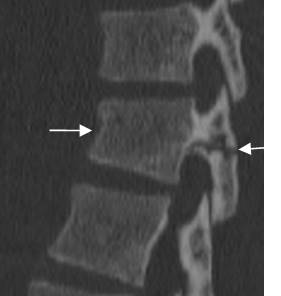

Fig 182. Fractura de Chance.

Fractura transversa y no desplazada, en el cuerpo vertebral y los elementos posteriores.